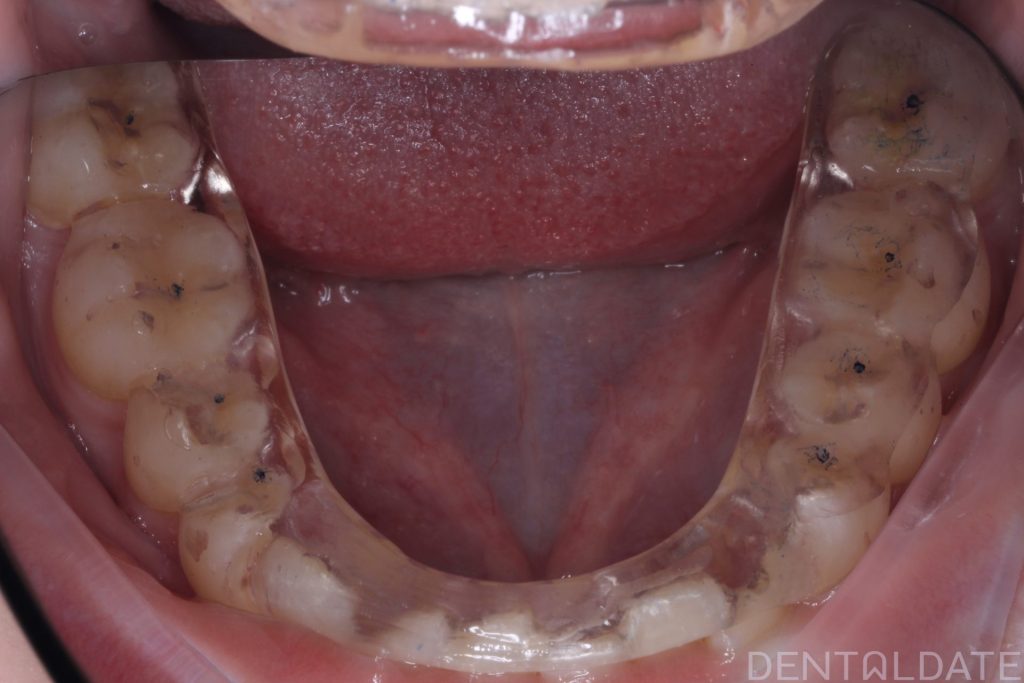

Orthodontic treatment lasted 10 months; currently, the patient is preparing for braces removal.